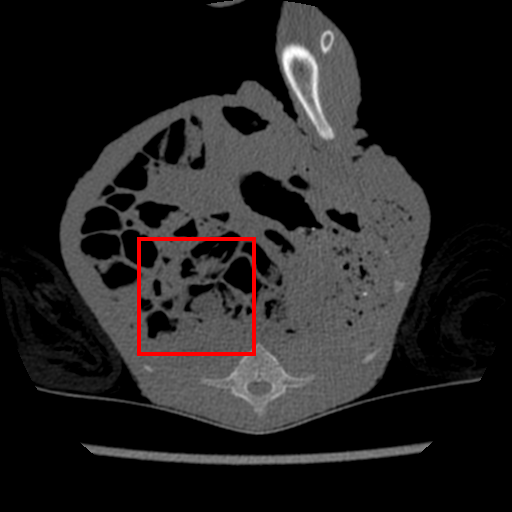

The same evaluation is performed for the supervised- and transfer-learning. Comparing with these two algorithms, it is clear that our approach delivers the highest PSNR. Although the results from transfer learning are closer, the difference is significant based on the t-test as we show in Sec. 4.4. Since this is the only experiment where we have access to a relatively large training set containing pairs of clean and real noisy data, we check the upper bound performance for our approach, which is the supervised learning performance using this large training set. Note that such full supervision violates one of our three assumptions mentioned in Sec. 1 – in particular, the one regarding the availability of a large number of training samples. Supervised learning achieves 40.28dB for and 38.84dB for , when trained with clean and real noisy training data. Our results in Table 1 indicate that we are close to this upper bound, although we train with synthetic training data. To further explore our approach, we meta-train it with clean and real noisy training data. Notably, our meta-denoising reaches 40.47dB for and 38.31dB for . This result shows the potential of meta-learning to become the standard training algorithm for the task of denoising. We present visual results in Fig. 1.